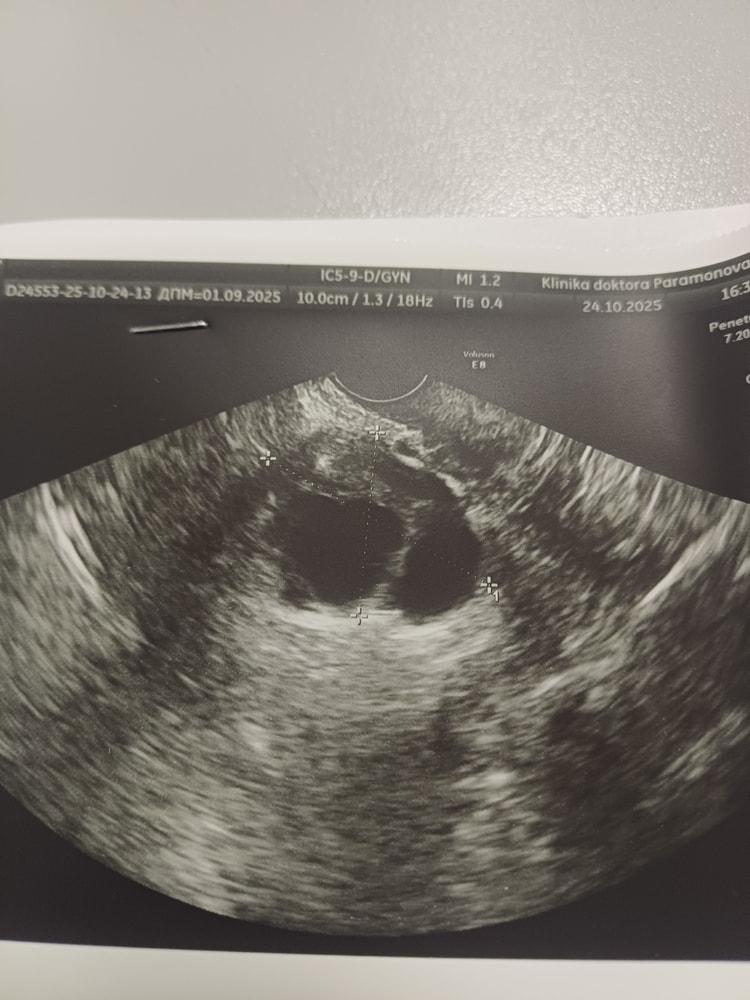

Девочки, вы тут чего только не видели. Может и тут кто подскажет. Идет 38 день цикла. Для меня это много. Второй цикл после лапары. Сделала узи. Говорят фоликулярные кисты поэтому и задержка. Узиска говорит должно болеть и знобить. А я себя отлично чувствую. И вот вопрос? Похоже на фоликулярную или нет?